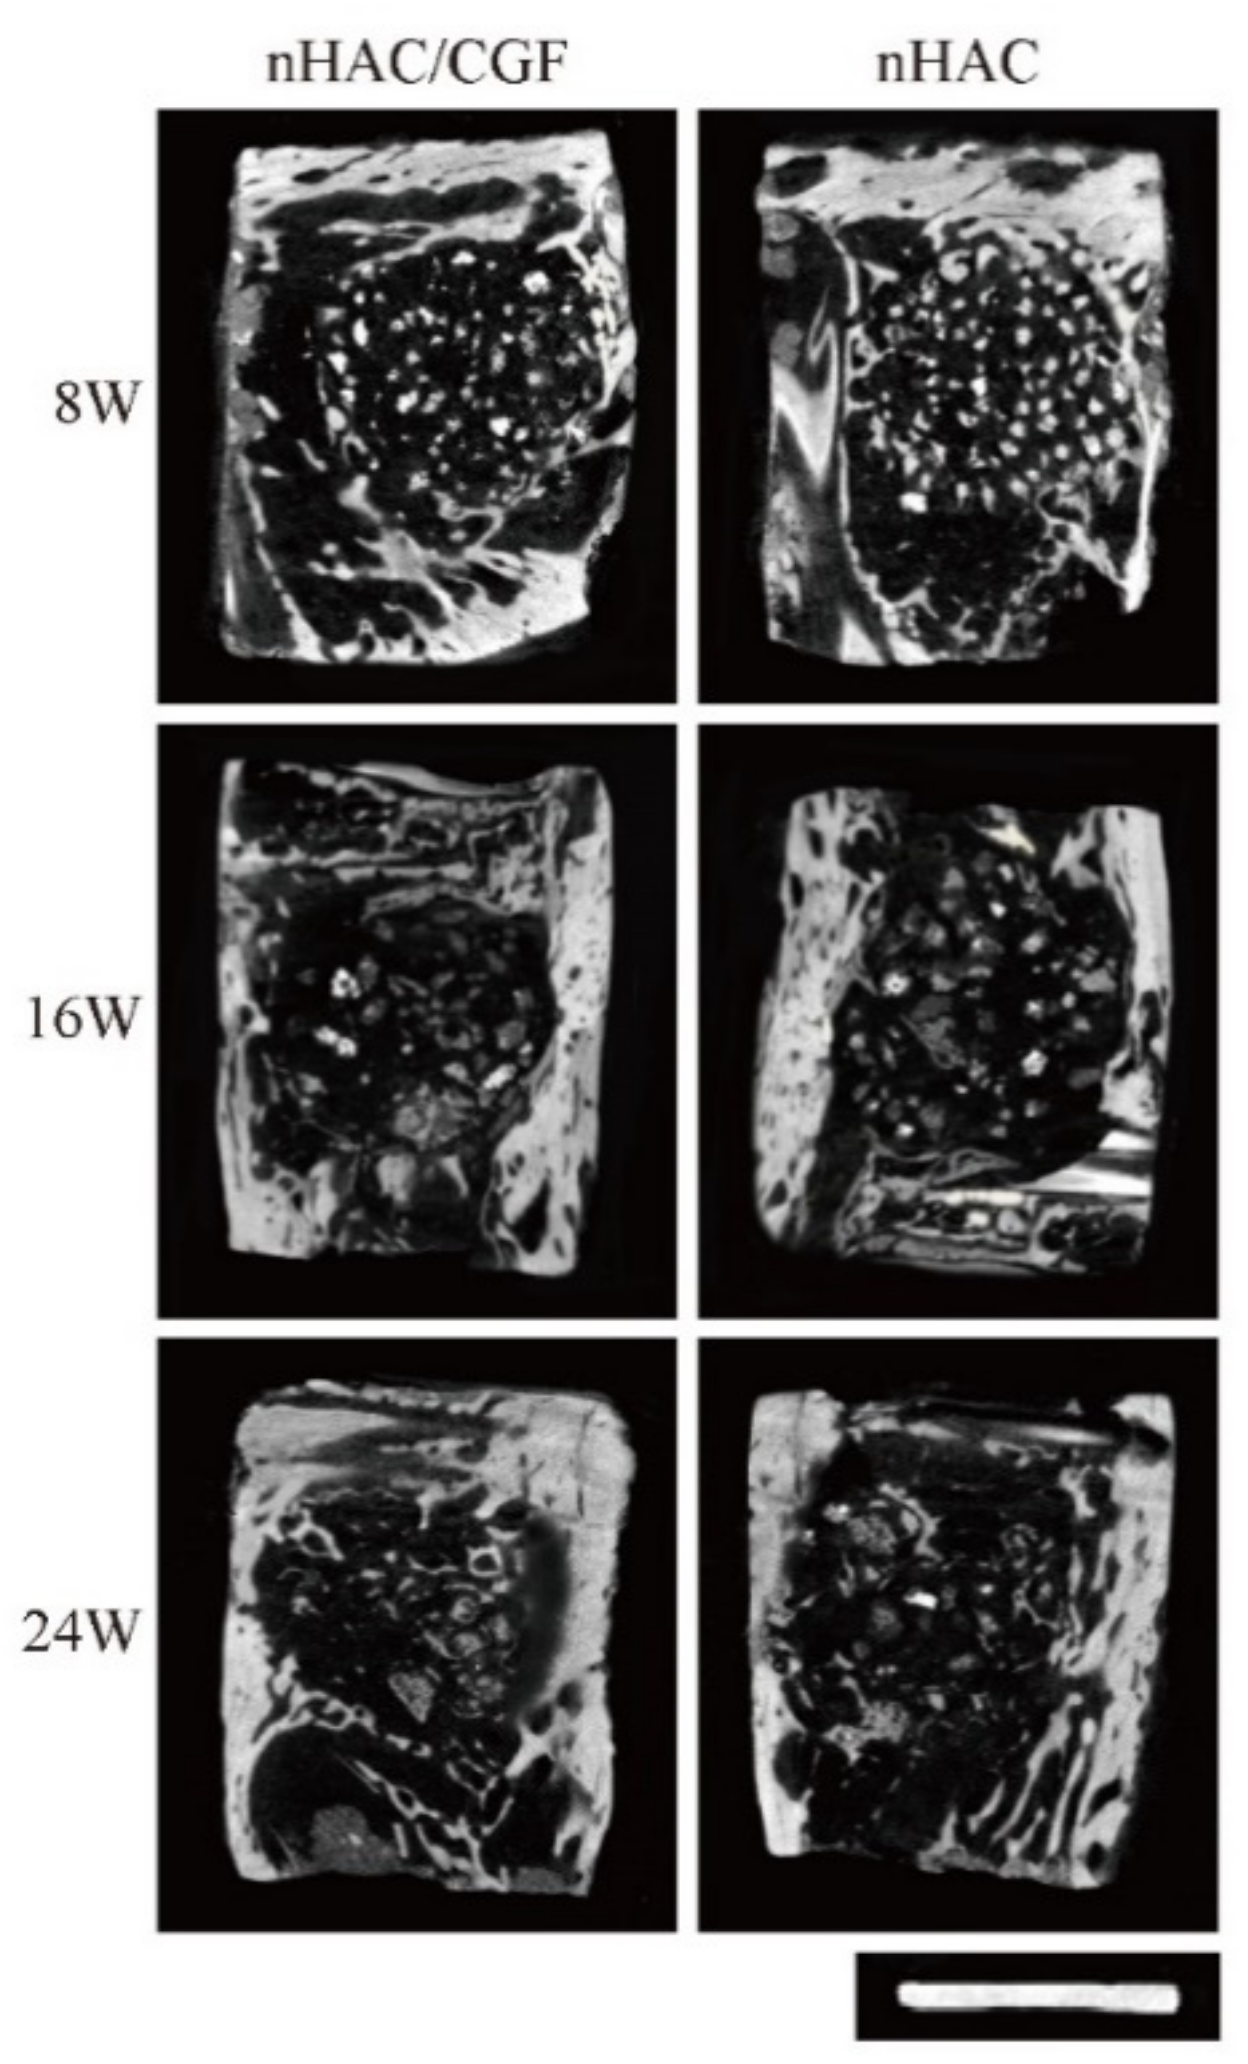

3.3. Imaging Testing